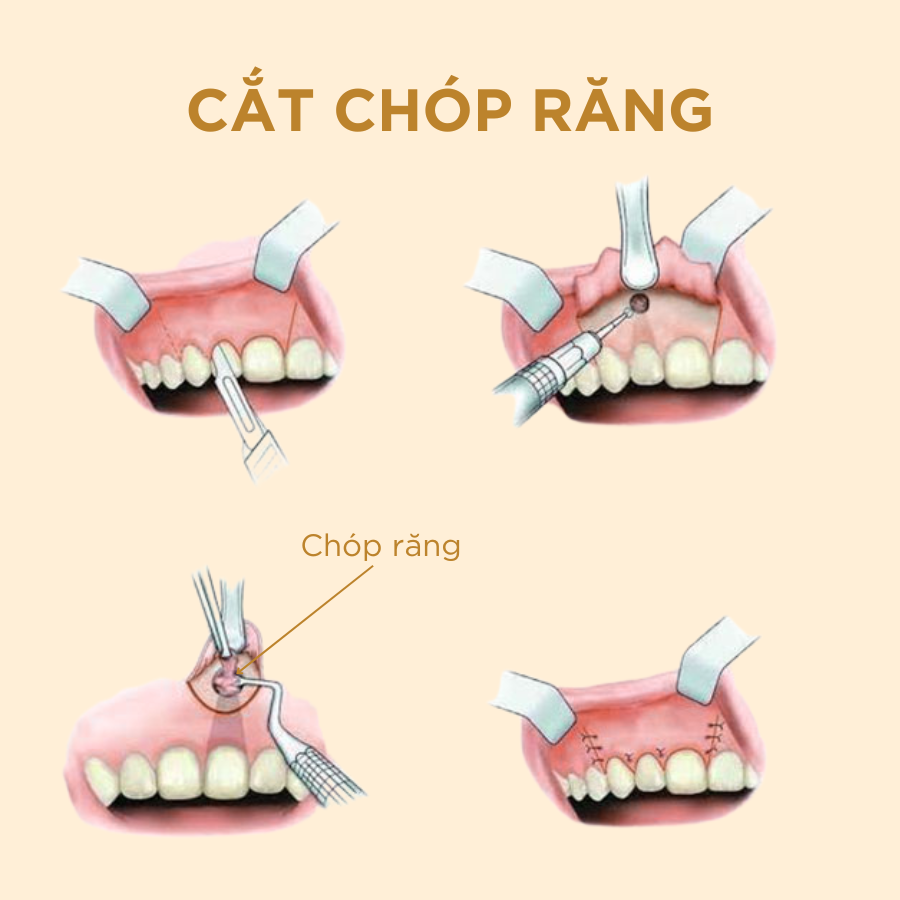

Cắt chóp răng

Cắt chóp răng là một tiểu phẫu nha khoa nhằm loại bỏ phần chóp và vùng viêm quanh chóp chân răng . Cắt chóp răng giúp giữ lại răng thật, chỉ xử lý vùng bị viêm nhiễm, từ đó bảo tồn răng và chức năng ăn nhai cho bệnh nhân.

QUY TRÌNH CẮT CHÓP Răng

- 1. Khám và tư vấn: Bác sĩ sẽ thăm khám lâm sàng và chụp X-quang để xác định mức độ nhiễm trùng và vị trí chính xác của vùng viêm. Điều này giúp bác sĩ lên kế hoạch phẫu thuật một cách chi tiết và an toàn.

- 3. Gây tê, tiếp cận và cắt chóp chân răng: Trước khi bắt đầu quy trình, vùng cần điều trị sẽ được gây tê để đảm bảo bạn không cảm thấy đau hoặc khó chịu trong suốt quá trình điều trị. Bác sĩ sẽ tạo đường vào vị trí chóp răng bị nhiễm trùng, loại bỏ khoảng 2mm phần chóp răng, đồng thời làm sạch mô viêm xung quanh.

- 4. Trám ngược chóp răng và khâu đóng vết mổ: Sau khi vùng viêm đã được làm sạch, phần cuối của ống tủy sẽ được trám bít ngược lại bằng vật liệu chuyên dụng để ngăn chặn sự tái nhiễm trùng. Vết mổ sẽ được khâu đóng và lành lại trong vài tuần sau đó.

- 5. Theo dõi và chăm sóc sau phẫu thuật: Sau điều trị, bạn sẽ được hướng dẫn cách chăm sóc vết thương và kê toa thuốc. Bác sĩ sẽ hẹn lịch tái khám cắt chỉ và kiểm tra quá trình hồi phục